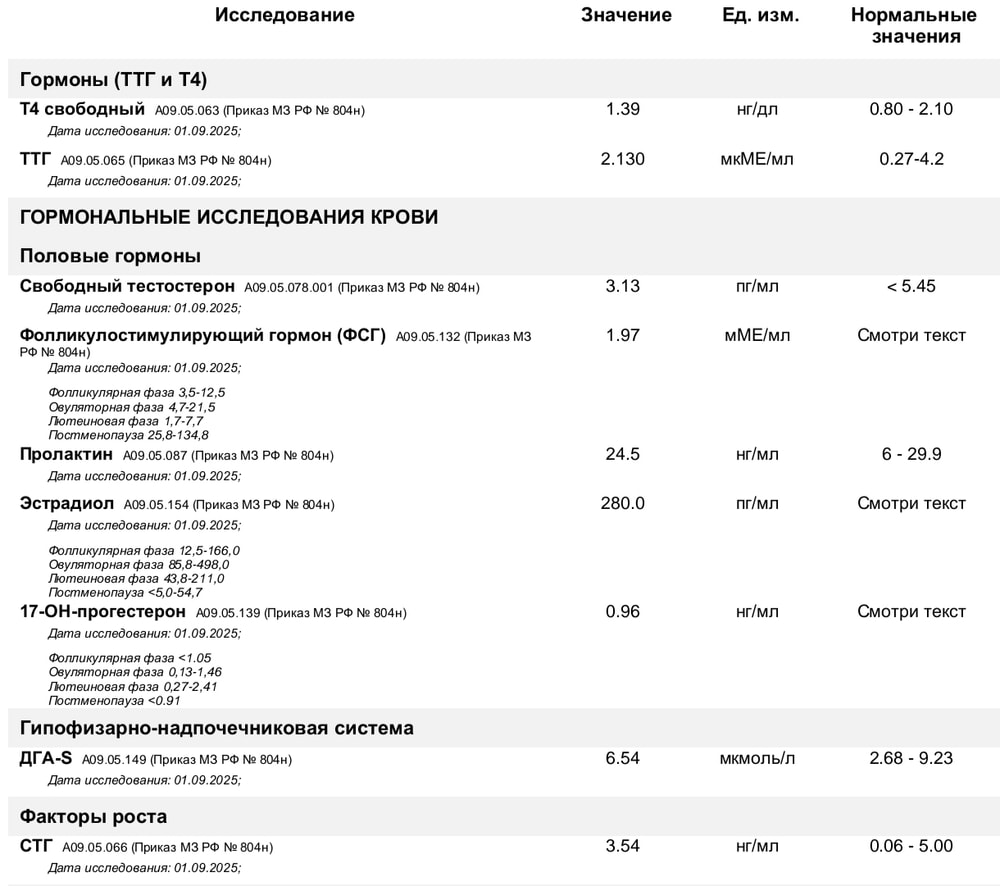

Собираю анализы на перенос и офигела - по гормонам какая-то лажа, а на УЗИ фоллик. киста! Эндометрий толстенный - 10 мм, как будто 2я фаза ещё не кончилась